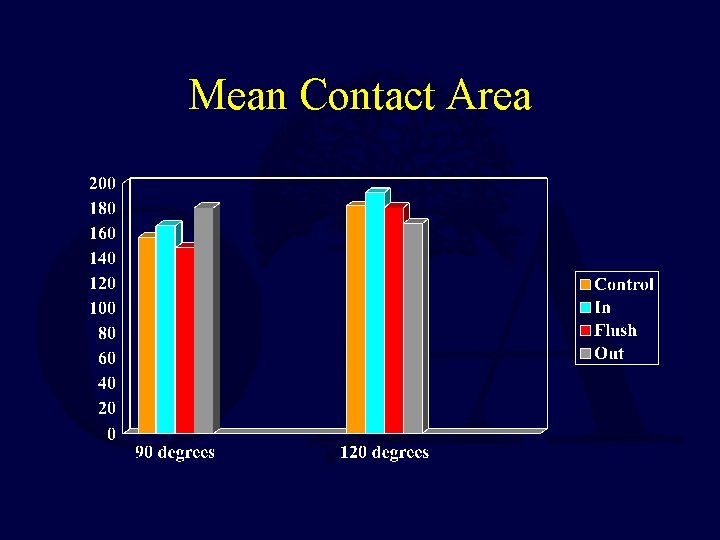

Mean Contact Area

Maximum Pressure * p < 0. 05 Only with the nail 1 mm prominent were the patellofemoral pressures increased

Retrograde Femoral Nailing • A cadaveric study using Fuji film demonstrated NO deleterious effects on the patello-femoral joint with a properly inserted retrograde IM nail • The orthopaedic literature does NOT support decreased knee motion or increase knee pain with a retrograde nail